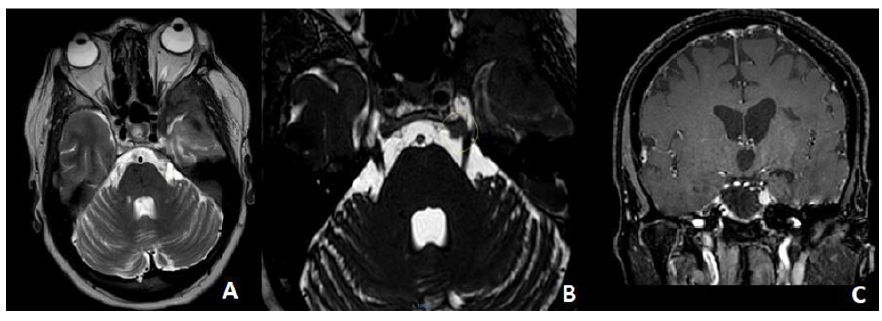

Uncommon but Unmistakable: A Case Report of Meckel’s Cave Meningioma

Siham Oukassem, Yassine Zerhari, Hatim Essaber, Asaad El Bakkari, Soukaina Allioui, Hounayda Jerguigue, Youssef Omor and Rachida Latib. 15(5): 57-58.